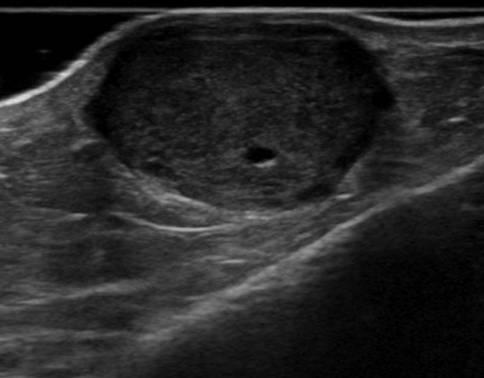

U máu

» Thông tin: Nam giới – 66 tuổi.

» Lâm sàng: Sưng cẳng chân.